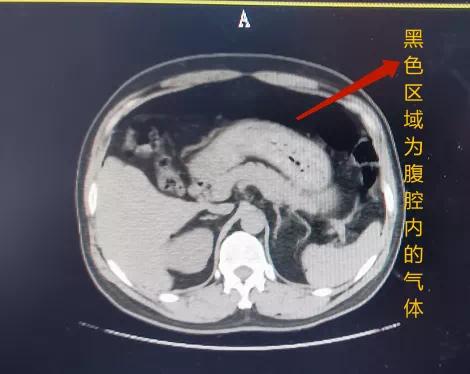

高压气体一旦进入人体

首先遭殃的就是 直肠、结肠、盲肠

别看它们加起来的长度

能顶好几个挺直站立的比比

可 正常厚度也只有 1-4mm